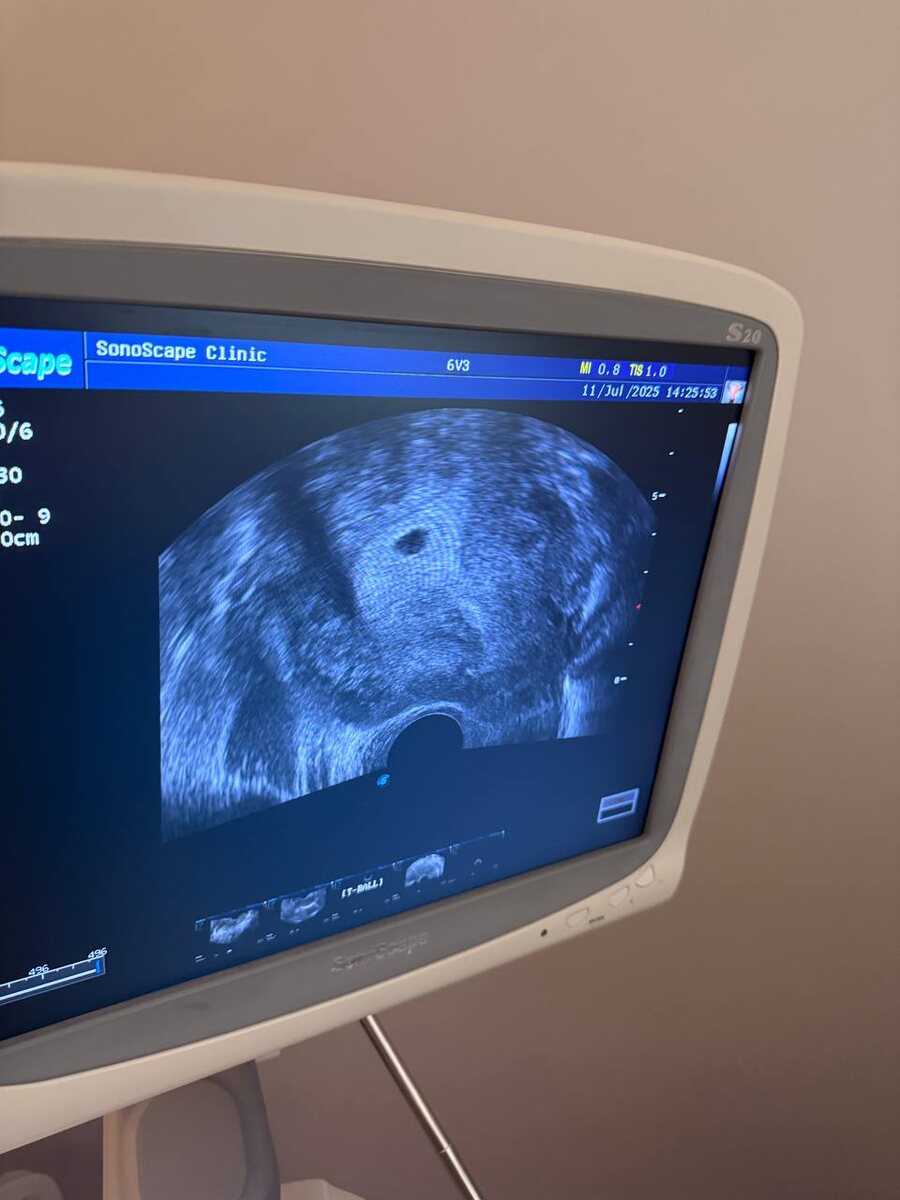

Беременность наступила после первой программы ЭКО (омс) по «стандартному» протоколу, пациентке 35 лет.